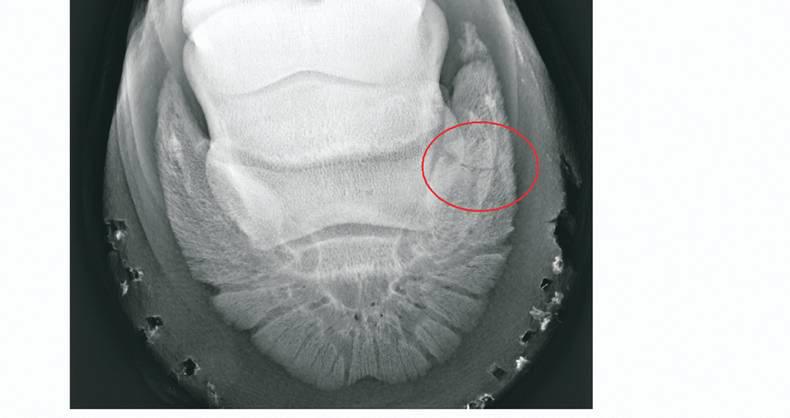

Within the hoof there are two main bones, the pedal bone and the smaller navicular bone. The pedal bone is the large bone that attaches to the hoof wall and provides strength and stability. The navicular bone meanwhile is a small bone, which lies behind the pedal bone.